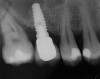

A 45-year-old female was referred for implant placement and prosthetic treatment in the area of tooth No. 24. The tooth had been extracted 4 years prior; the patient did not wear any denture thereafter. The radiograph revealed adequate bone height and a 5-mm to 6-mm ridge at the crest (Figure 2). It was decided to place a 11.5 mm in length, 3.75 mm in diameter Tapered Screw-Vent® implant (Zimmer Dental, www.zimmerdental.com) using the alveolar remodeling technique in the area of tooth No. 24.

Figure 2 Preoperative view of the area around tooth No. 24. On the left, a previously placed implant abutment

is visible.

Figure 4  Implant positioning; the radiograph taken 4 weeks after placement confirmed good primary stability.

Figure 4